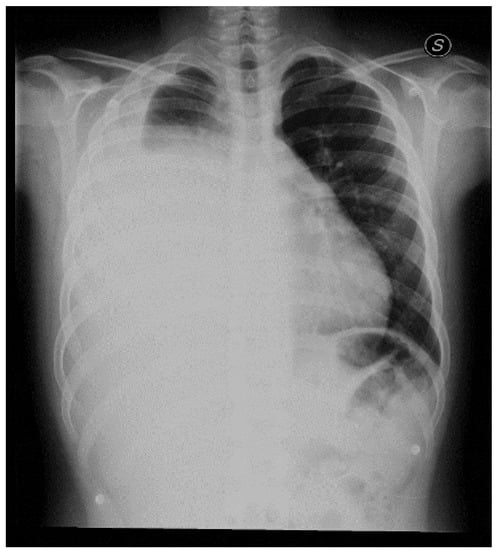

2. Case Report